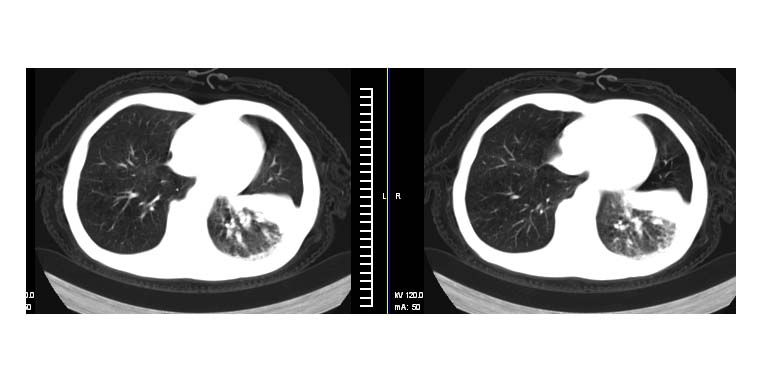

标题: CT11019:男性,66岁。发烧5-6天。治疗后无明显好转。 [打印本页]

标题: CT11019:男性,66岁。发烧5-6天。治疗后无明显好转。

左侧胸廓偏小,左下梭形高密度影,考虑阻塞性肺炎.

斜肋积液

斜裂积液,炎症

明明是斜裂胸膜积液,为何都考虑阻塞性肺炎、肺不张(边缘内凹,而本例是外凸)。